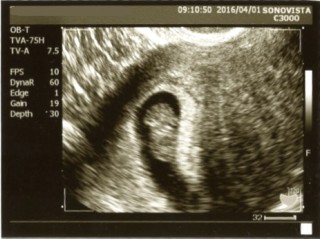

2回目の受診でした。 今回は赤ちゃん本体だけでなく心臓が動いているところも見れて一安心でした。 大きさは20.9mm。 出産予定日も決まり、自分の計算ととりあえずはぴったりだったのである程度の予定はたてられそうです。 そろそろお互いの両親にも報告しようかと旦那と話しています。 次の診察まで体調に気をつけて過ごしたいと思います。

心配で2週間待てず10日後に2回目受診。18.8mm。大きく育っていて心拍も前回よりはっきり確認できました。私みたいにせっかちなのかな予定日が初診のときより8日早くなりました。出生前診断について聞かれたけれど仮にダウン症等であっても大事に育てたい。主人と決めて検査はしない事に。

2度目の検診。 1度目で心拍は確認出来たのですが、 もう一度確認してから 母子手帳の交付ということでした♪ 無事心拍確認できました。 赤ちゃんの大きさは2cmくらいかな? 手足の確認も出来ました♪ 次は2週間後。

念願の3人目。 2週間ぶりの検診でドラえもんに変身してました!かわいい… 3人目でもやっぱり検診日は待ち遠しくてウズウズしちゃいますね! ベビたんの大きさは1.91センチでした!